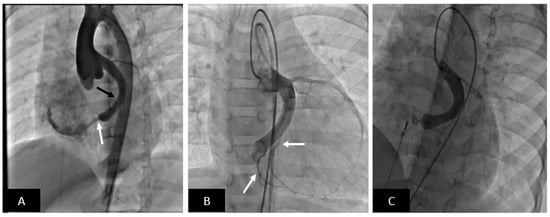

2.2. Endovascular Stenting of Obstructed Blood Vessels

- Acute risks include access site vascular injury, stent migration, implantation site vascular injury, need for emergency surgery, compression of adjacent vascular structures (coronary artery compression during right ventricular outflow stenting or the airway, left bronchial compression during left pulmonary artery stenting after Fontan palliation), and rarely death.

- Fortunately, most stents can be safely dilated beyond manufacturer-recommended maximum diameter to accommodate for somatic growth (note that self-expanding stents cannot be dilated beyond nominal diameter). To accomplish this, serial incremental dilation is necessary. All stents dilated beyond the nominal diameter shorten longitudinally, with the degree of shortening being stent-specific and widely variable.

- Small children are frequently treated with pre-mounted small and medium diameter stents owing to the necessity for a smaller crossing profile and flexibility. Here the only option for increasing stent diameter is surgical intervention or intentional stent fracture followed by placement of a larger stent. While feasibility has been shown on the bench and in some clinical studies, the generalizability of this approach is awaiting real world clinical data.